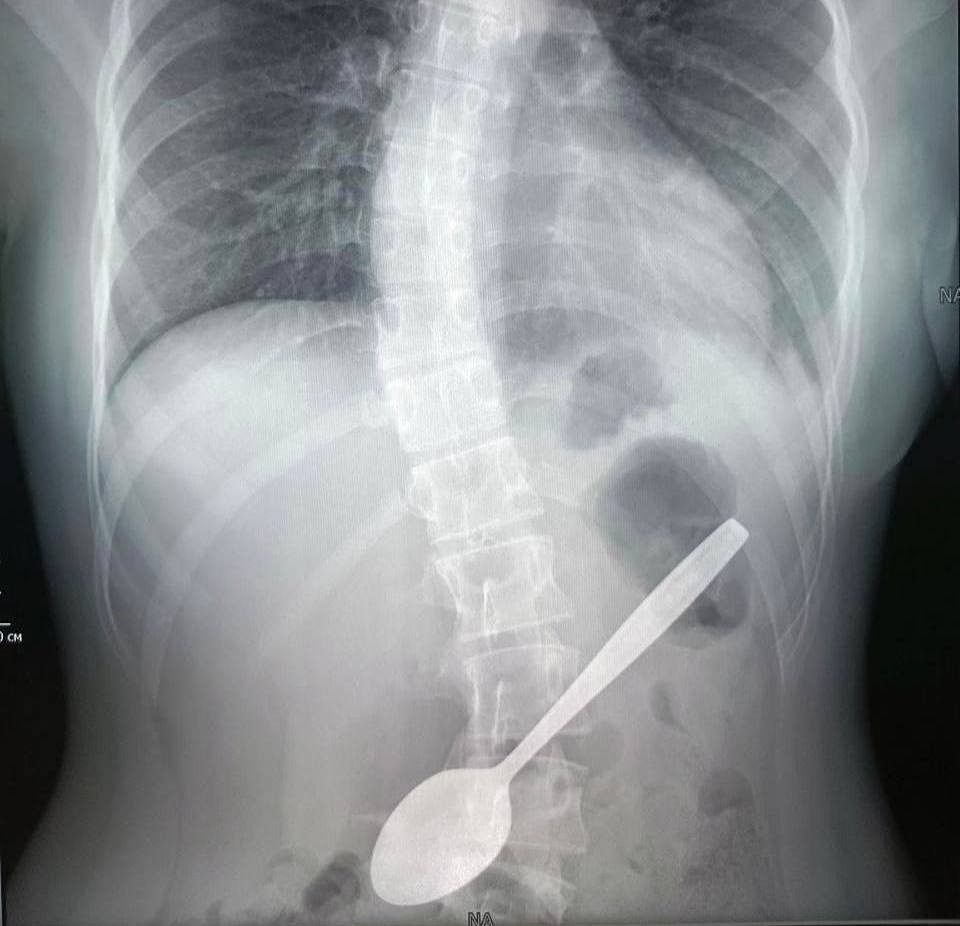

Как школьница проглотила ложку?

В одном из подмосковных населённых пунктов 14-летняя ученица школы случайно проглотила чайную ложку длиной 15 сантиметров. Причиной инцидента стало то, что девочка пыталась достать застрявшее в горле яблоко. Ребёнка доставили в больницу, где врачи провели операцию по извлечению столового прибора. Для этого была использована эндоскопическая техника. Процедура заняла примерно 60 минут.